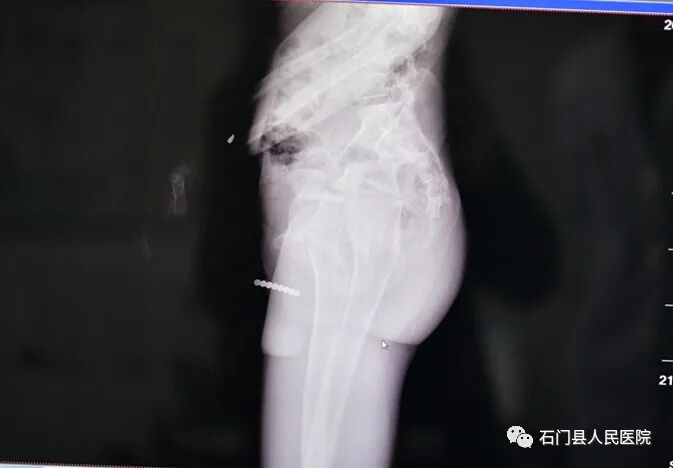

据父母介绍,林林活泼好动,是家里的开心果,可是前几天林林一直哭闹,喊着肚子痛,家人将他送往医院后,经过详细检查,发现肠子里有异物。林林被紧急转往我院胃肠外科十病区治疗。

同时术中在肠内取出了导致林林肠穿孔的罪魁祸首——9颗磁力珠!

近些年,磁力珠玩具非常流行,但是因磁力珠造成的伤害也层出不穷,医生介绍,磁力珠不同于普通的异物,珠子因磁力吸引相互连在一起夹挤肠管,所以它们不会像硬币、螺丝帽等随着大便排出,反而都会导致肠穿孔一旦穿孔后的肠内容物溢出至腹膜腔,可能会引起弥漫性腹膜炎,除了剧烈腹痛、腹胀等症状,严重的会导致休克甚至死亡。所以对没有判断能力的孩子来说,磁力珠是很危险的玩具。